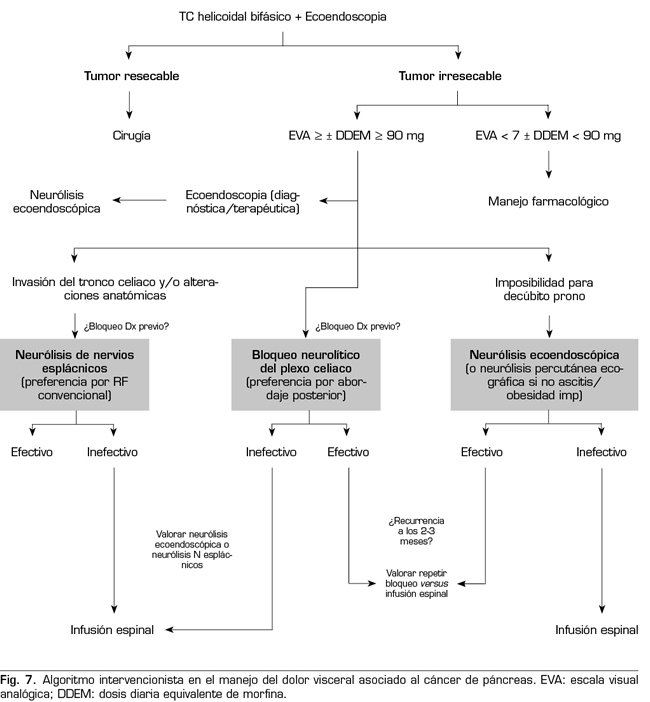

PROPUESTA DE ALGORITMO INTERVENCIONISTA

El manejo del dolor asociado al cáncer de páncreas debería ser, como en cualquier otro tipo de dolor oncológico, un manejo multidiscilplinar. Esto exige de una estrecha colaboración entre los servicios de oncología médica, oncología radioterápica, cirugía, digestivo, cuidados paliativos y dolor, ya que la evolución de la enfermedad provoca que estos pacientes se sometan a diferentes pruebas y tratamientos que pueden influir en la toma de decisiones. La ecoendoscopia puede ser necesaria no solo en el momento del diagnóstico, sino también en otras situaciones a lo largo de la enfermedad como, por ejemplo, para diagnosticar complicaciones. Por tanto, tendrá que haber un trabajo en equipo para aprovechar esta técnica y realizar la neurólisis en ese momento si está indicada, para evitar así un mayor sufrimiento a los pacientes con más técnicas intervencionistas innecesarias. Otras consideraciones a tener en cuenta son que algunos tratamientos quimioterápicos pueden producir alteraciones de la hemostasia, a tener en cuenta para la selección del abordaje percutáneo, y que el uso de radioterapia puede mejorar el dolor tumoral, otro motivo más para llevar a cabo un manejo multidisciplinar y ordenado. Por último, es aconsejable una valoración psicológica de los pacientes para controlar factores que pueden disminuir el umbral del dolor, como son la angustia, la ansiedad o la depresión asociadas, ya que pueden influir en la valoración de la EVA y en la decisión final del bloqueo neurolítico.

Siguiendo las conclusiones de las publicaciones previamente descritas, se puede establecer un algoritmo de tratamiento intervencionista de los pacientes con dolor visceral asociado al cáncer de páncreas (Figura 7).

El procedimiento estándar sería el abordaje posterior del plexo celiaco (abordaje clásico), ya que a día de hoy continúa siendo el de mayor evidencia científica, preferiblemente transcrural y guiado por fluoroscopia, debido a su sencillez y rapidez. La ecoendoscopia estaría indicada para la neurólisis aprovechando su indicación diagnóstica o terapéutica, para situaciones de imposibilidad para el decúbito prono, y como alternativa en caso de que falle el abordaje posterior. La neurólisis percutánea ecográfica quedaría reservada para casos seleccionados, dependiendo de la experiencia del operador, ya que es la técnica que menos publicaciones tiene hasta la fecha. Confiamos en que en un futuro se publiquen trabajos que permitan a las técnicas ecoguiadas, ya sean percutáneas o ecoendoscópicas, ocupar el puesto de “método de referencia”, ya que permiten la visualización de las estructuras circundantes con control de la inyección en tiempo real. Una alternativa al bloqueo del plexo celiaco es la radiofrecuencia convencional de los nervios esplácnicos, indicada cuando existe infiltración tumoral del tronco celiaco, alteraciones anatómicas importantes o si fracasa la neurólisis del plexo celiaco. También es posible considerar una neurólisis combinada —bloqueo neurolítico del plexo celiaco asociado a bloqueo neurolítico o radiofrecuencia de los nervios esplácnicos—, como refleja el trabajo de Marra y cols. (60), y como venimos realizando en nuestra práctica clínica habitual en HM hospitales, con el objetivo de aumentar la tasa de éxito y la duración de la analgesia sin aumentar la incidencia de complicaciones, pero hasta ahora no hay trabajos comparativos suficientes para apoyar esta hipótesis (Figura 8).

Respecto al momento idóneo para realizar el bloqueo, nuestro equipo aboga por una neurólisis que no sea tardía a pesar de que la duración del efecto es limitado, ya que vemos una serie de ventajas en los pacientes, como son un mayor control del dolor, una mejora en la calidad de vida, y una menor tolerancia a opioides. Lo que sí es mandatorio, como indica una de las principales variables para realizar la neurólisis, es que el dolor sea severo, que según la OMS se estima en un EVA > 7. Los pacientes con cáncer de páncreas y dolor severo que se sometan a procedimientos neurolíticos, deben estar previamente tratados con opioides potentes, pudiendo establecer una dosis diaria equivalente de morfina (DDEM) por encima de 90 mg para confirmar la decisión del bloqueo, o menor si el paciente padece efectos secundarios importantes derivados de los opioides.